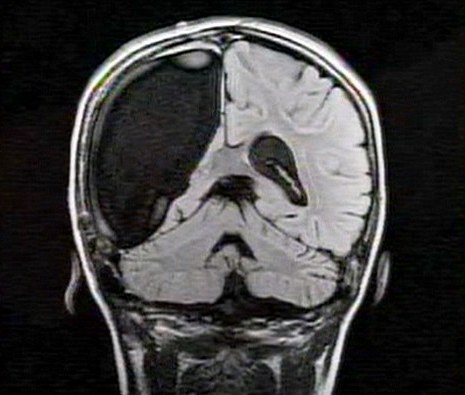

中新網(wǎng)3月26日電 據(jù)英國媒體26日?qǐng)?bào)道,一名9歲的英國女孩在經(jīng)歷了右腦切除手術(shù)后奇跡康復(fù),令醫(yī)生和家人無比震驚。

報(bào)道稱,現(xiàn)年9歲的卡梅倫•莫特在手術(shù)中切除了她整個(gè)右半邊的大腦,而在經(jīng)歷如此重大的手術(shù)后能迅速康復(fù),莫特的奇跡也讓醫(yī)生和她的家人驚嘆不已。年幼的莫特也沒有因?yàn)椴“Y而放棄對(duì)夢(mèng)想的追求。

卡梅倫莫特在3歲那年患上一種被稱作大腦功能紊亂“拉斯穆森”綜合癥,這種病癥誘發(fā)患者的無序暴力行為和嚴(yán)重的癲癇。醫(yī)生建議,治療這種病癥只能通過嘗試消除引發(fā)此癥狀的大腦組織。而手術(shù)讓莫特失去了幾乎整個(gè)半邊的大腦。

據(jù)悉,莫特在手術(shù)后已經(jīng)可以跑動(dòng)和玩耍,她在術(shù)后的第四周離開了醫(yī)院。醫(yī)生表示,雖然右半邊大腦的切除可能會(huì)給莫特帶來半身不遂的風(fēng)險(xiǎn),但孩子剩余的大腦仍具有很強(qiáng)的重組和布線能力。